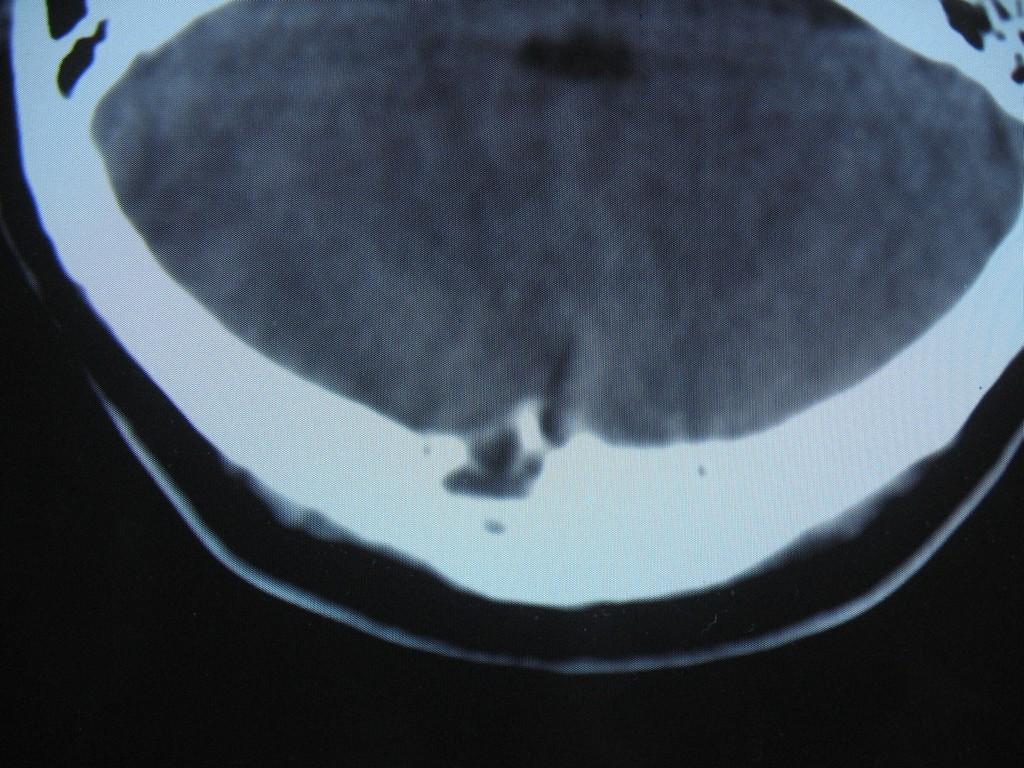

标题: CT22032B:枕骨破坏(从新调整窗宽窗位) [打印本页]

标题: CT22032B:枕骨破坏(从新调整窗宽窗位)

女性病人,53岁,偶尔感枕部针刺样疼痛,ct扫描如下。

蛛网膜颗粒压迹。鉴别:骨巨,嗜酸性肉芽肿,骨髓瘤。

蛛网膜颗粒压迹。

骨巨,嗜酸性肉芽肿,骨髓瘤,动脉瘤样骨囊肿可能

支持蛛网膜颗粒压迹,嗜酸性肉芽肿发生于30岁以下,基本排除,骨髓瘤、转移瘤多伴有软组织肿块,范围较广。

枕骨蛛网膜颗粒压迹。